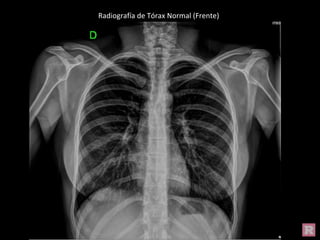

Radiografía de Tórax Normal (Frente)

Estructuras óseas en Radiografía de Tórax (Frente)